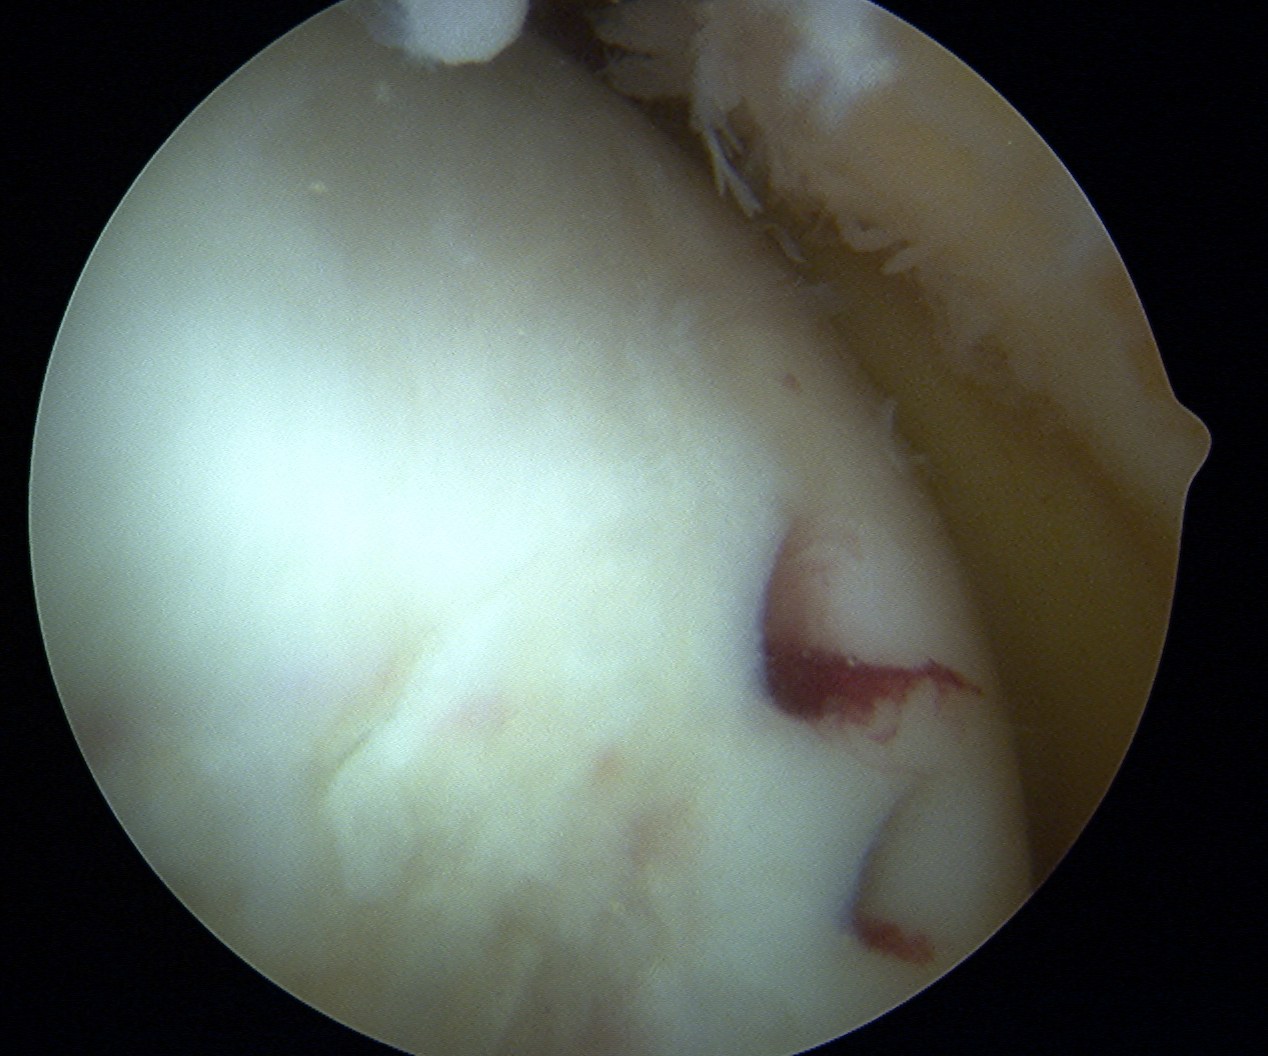

Debride base of OCD and reduce

Repeat

Post op

Often most stable in extension

- splint in extension 2 weeks

- gentle increased ROM in brace over next 4 weeks

- strict NWB 6/52

Allow weight bearing at 6/52

- no sports for 6/12

- MRI cartilage sequences at 3 and 6 months to assess cartilage healing